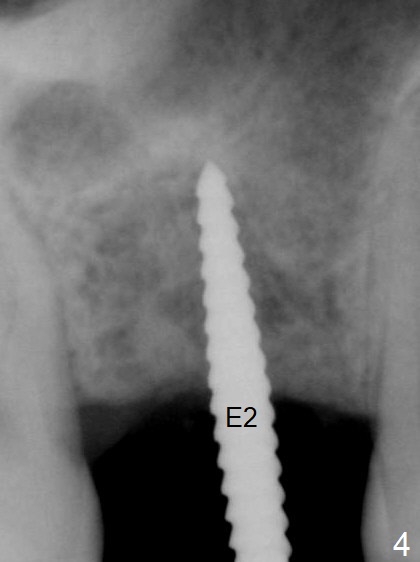

A 54-year-old man has lost the tooth #3 for 6 months with complicated sinus floor morphology (Fig.1 red dashed line (one of 2 outlines), bone height ~ 7 mm). Initial osteotomy depth is ~ 6 mm (Fig.2,3 with 1.2 mm initial drill and DIO Bone Expander 1 (E1 with diameter 1.0/1.6 mm). Following change in the trajectory, E2 (1.3/2.3 mm) is used for ~ 8 mm (Fig.4). After application of E4 (2.4/3.7 mm, Fig.5) and E5 (3.0/4.4 mm) for ~ 12 mm, the sinus membrane is found to have perforated. With placement of collagen membrane and cortical allograft (Fig.6 *), a 5x8.5 mm Hiossen implant is placed with >50 Ncm.